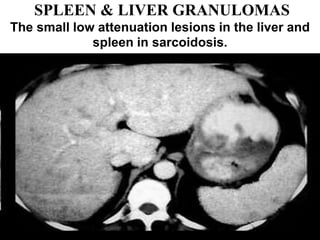

SPLEEN & LIVER GRANULOMAS

The small low attenuation lesions in the liver and

spleen in sarcoidosis.